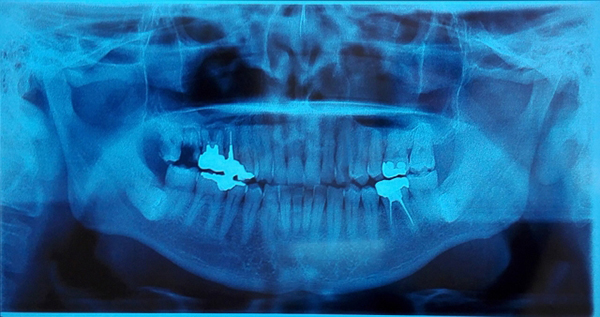

抜歯をする場合、どの位置の歯がどのような埋まり方をしているかにより、治療の難易度が変わってきます。

大人の歯が、歯ぐきや歯槽骨の中に埋まっている状態が埋伏歯と呼ばれます。

必要があれば、歯茎を切開して歯を取り出します。

埋伏歯の周りの神経や血管の位置によっては、一般的な抜歯と比べはるかに高い技術が要求されます。